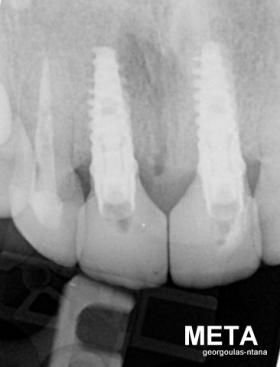

ΤΟΠΟΘΕΤΗΣΗ ΕΜΦΥΤΕΥΜΑΤΩΝ ΣΤΗΝ ΠΕΡΙΟΧΗ ΤΩΝ ΑΝΩ ΤΟΜΕΩΝ

Στην ασθενή αυτή είχαν πραγματοποιηθεί 2 ενδοδοντικές θεραπείες (απονευρώσεις) που ακολουθήθηκαν από 2 ακρορριζεκτομές χωρίς επιτυχία. Η ασθενής ήταν δυσαρεστημένη με την όψη κ το χρώμα των δύο δοντιών και φυσικά με το πρόβλημα υγείας που δημιουργήθηκε. Πραγματοποιήθηκε εξαγωγή των δύο δοντιών, οστική αύξηση και τοποθέτηση 2 εμφυτευμάτων στις θέσεις των δύο κεντρικών τομέων. Τα δύο εμφυτεύματα αποκαταστάθηκαν με 2 υβριδικά κολοβώματα από διπυριτικό λίθιο και ολοκεραμικές στεφάνες ενώ στους 2 πλάγιους τομείς τοποθετήθηκαν επίσης ολοκεραμικές στεφάνες.